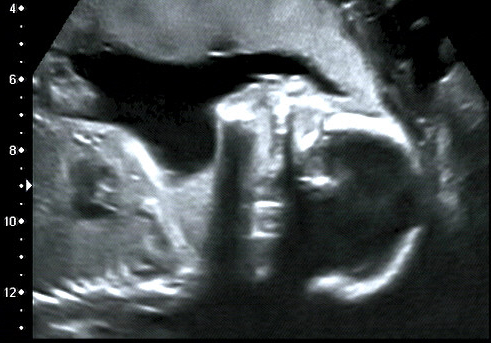

3-D-Ultraschallbild Januar 2011

Als ich aufgerufen werde, bin ich plötzlich doch etwas nervös. Schön, dass ich wiederholt vom Facharzt für Pränatal-Diagnostik betreut werde – er strahlt viel Ruhe und Erfahrung aus und nimmt sich Zeit für uns. Wir beginnen mit einem Lacher, denn als erstes liegt das Baby so, dass wir ganz klar sehen können, dass es ein Junge ist.

Ultraschallbikd des Gesichts

Schritt für Schritt werden die gesamten Organe angeschaut und immer wieder heißt es: alles sehr sehr gut, alles bestens! Ich freue mich und bin einfach nur dankbar. Es kann bereits gesehen werden, dass eine Frühgeburt mit sehr hoher Wahrscheinlichkeit ausgeschlossen ist und das Baby zeitgemäß zur Welt kommt.

Das heißt, dass wir unseren Nachwuchs circa zwei Wochen vor bis zwei Wochen nach dem Entbindungstermin am 15. Mai 2012 erwarten können. In meinen Mutterpass wird eingetragen, dass ich mich nun in Woche 21 plus 2 befinde. Also mehr als Halbzeit!